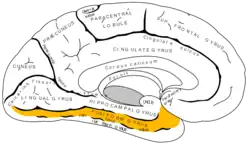

Giro fusiforme en amarillo, dentro del Lóbulo temporal. Vista interna del hemisferio izquierdo. | ||

El giro fusiforme o giro occípitotemporal lateral es una circunvolución cerebral, ubicada en la cara basal del lóbulo temporal. Es responsable del reconocimiento facial y su lesión provoca prosopagnosia, alucinaciones de rostro, sinestesia.

El giro fusiforme se encuentra en el lóbulo temporal en la superficie basal del hemisferio cerebral, entre el giro temporal inferior por fuera y el giro parahipocampal por dentro. [1]

El giro fusiforme esta limitado por dentro por el surco colateral y por fuera el surco occípitotemporal lo separa del giro temporal inferior.